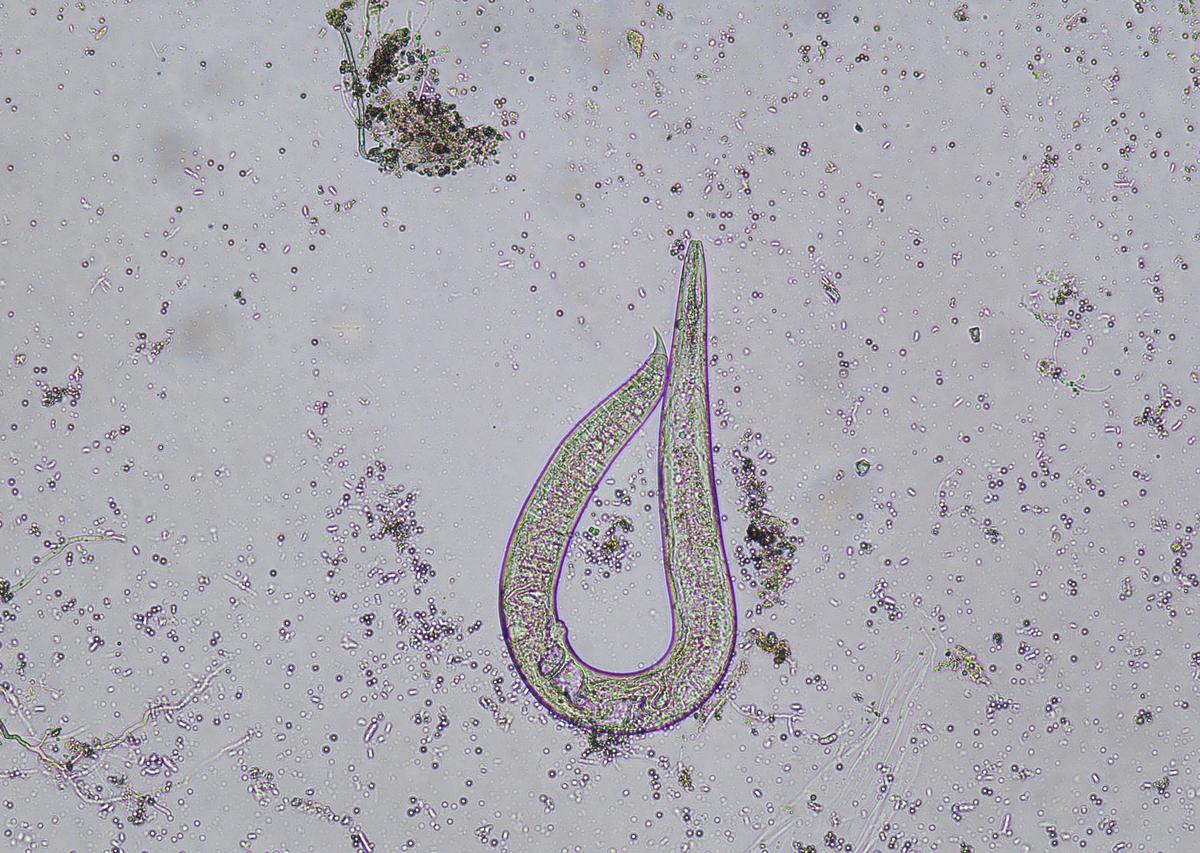

小明外出旅游时,决定考验自己的肠胃功能和肠胃免疫力。他找到了一条不太干净、发臭的河水,喝下了一口,不知道自己已经感染了贾第鞭毛虫。

最终,小明意识到他必须寻求医疗帮助。他前往当地医院,经过检查,确认他感染了贾第鞭毛虫并引起了严重的肠胃炎症。